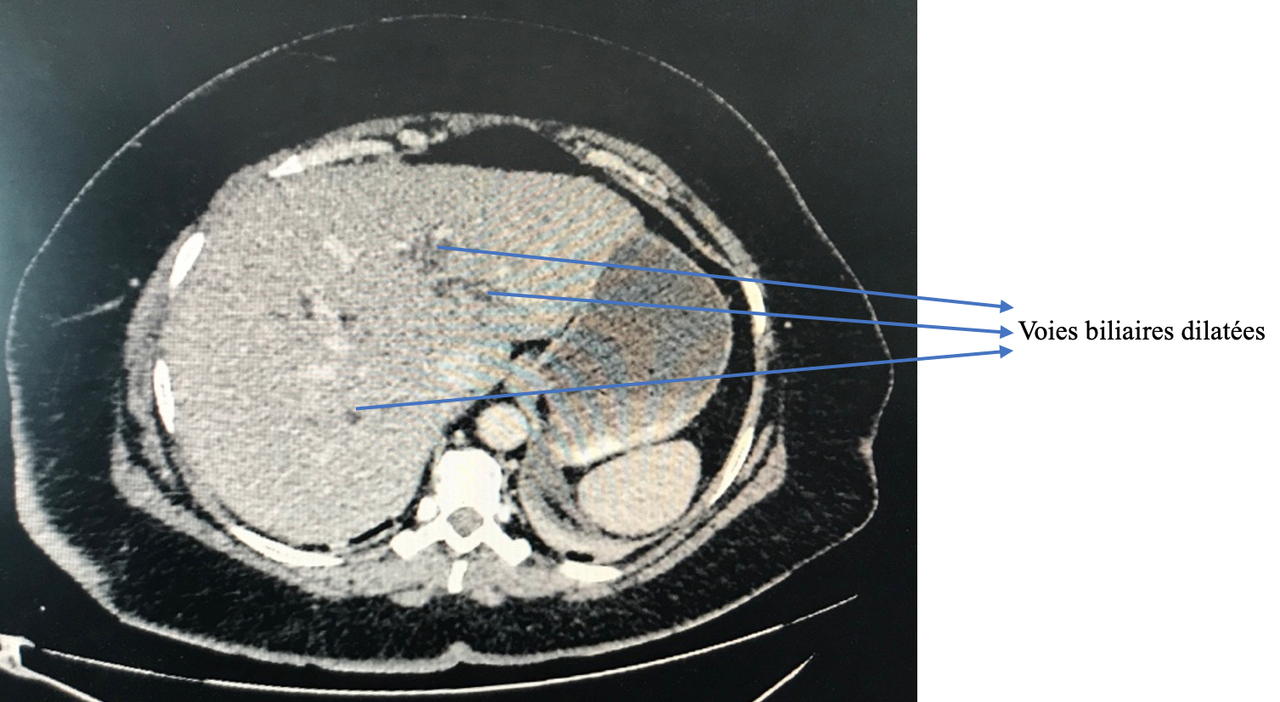

La cholécystite se traduit par un syndrome infectieux avec une douleur de l’hypochondre droit. C’est une possibilité.

La douleur de la pancréatite est épigastrique irradiant dans le dos, majorée par la respiration profonde et la position antalgique est en chien de fusil.